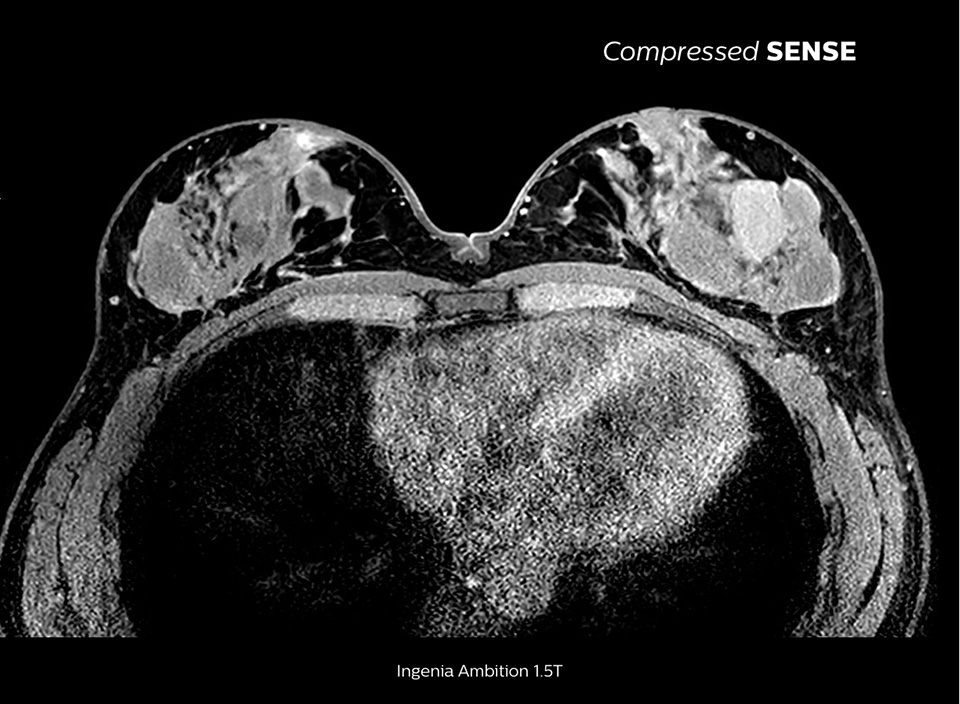

Up to 50% faster 3D sequences, with virtually equal image quality1

Compare the time savings of an MRI scan performed with Compressed SENSE MRI software versus a conventional scanning technique